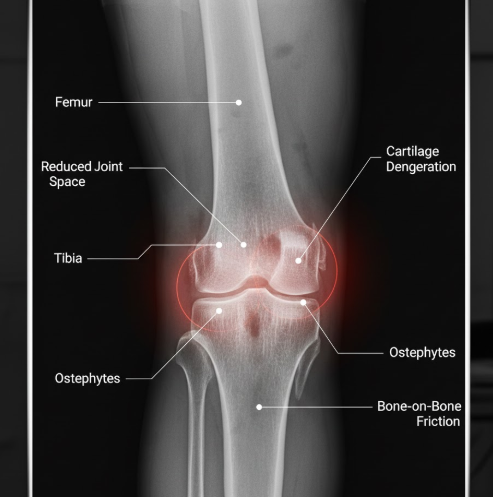

1) 퇴행성 관절염

50대 이상에서 가장 흔한 무릎통증원인은 바로 퇴행성 관절염입니다.

무릎 관절의 연골이 나이가 들면서 점차 닳아 없어지고, 뼈와 뼈가 직접 마찰하면서 통증과 염증이 발생합니다.

아침에 일어났을 때 무릎이 뻣뻣하고, 움직이기 시작하면 조금 나아지는 것이 특징입니다.

계단을 내려갈 때 통증이 심하고, 무릎에서 '드득드득' 소리가 나며, 날씨가 흐리거나 추울 때 증상이 악화됩니다.

퇴행성 관절염의 위험 요인으로는 비만이 가장 중요합니다.

체중이 1kg 증가하면 무릎에는 3~4배의 부하가 증가하므로, 과체중은 연골 손상을 가속화하는 주요 무릎통증원인이 됩니다.